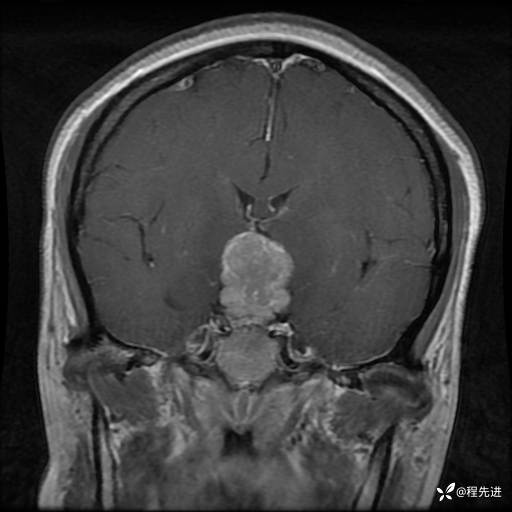

MRI平扫+增强:

T2:

T1+C: